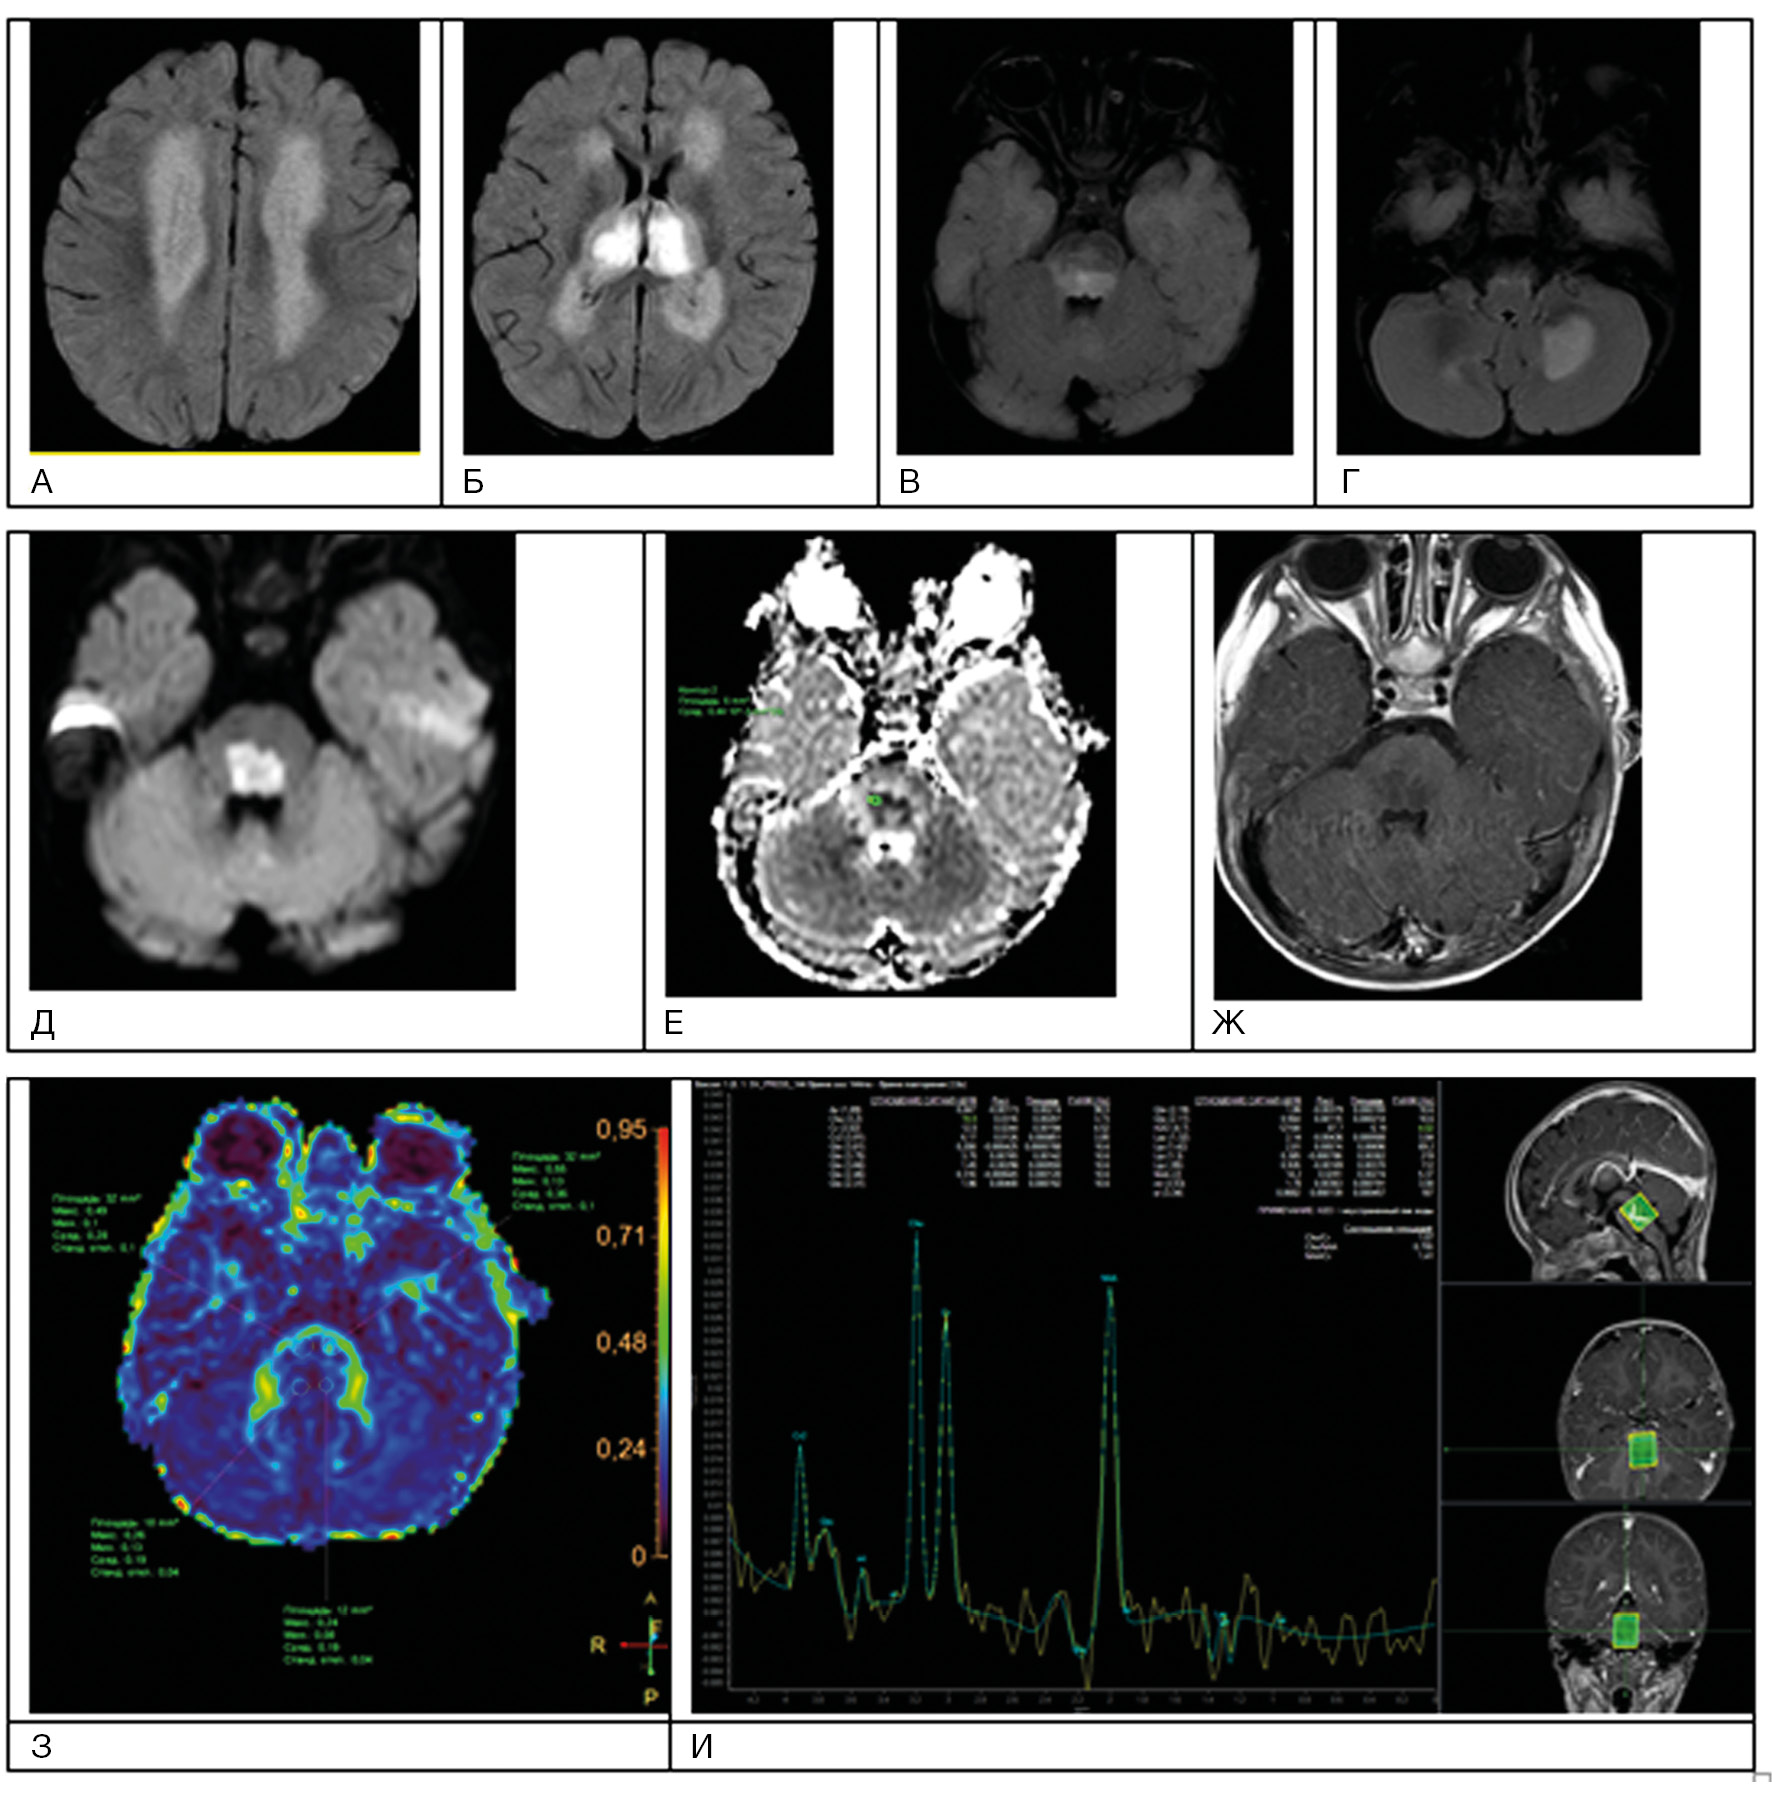

Острые нарушения мозгового кровообращения у детей в 5–6% случаев поражают ствол мозга [8, 9]. Эмболы попадают в артериальные терминали и приводят к появлению Т2-гиперинтенсивных очаговых поражений (рис. 1). Крупный очаг (более 50% диаметра ствола) является прогностически неблагоприятным признаком [9].

Рис. 1. Пациент А., 7 лет. МРТ: поражение ствола мозга в результате острого нарушения мозгового кровообращения по ишемическому типу в бассейне основной артерии, 2-е сут заболевания

Примечание. При магнитно-резонансной томографии (МРТ) в варолиевом мосту визуализируется зона патологического гиперинтенсивного МР-сигнала на Flair (А) без признаков нарушения гематоэнцефалического барьера при внутривенном контрастировании в зоне поражения (Б). На диффузионных последовательностях (В) визуализируется цитотоксический отек с признаками ограничения диффузии и значениями измеряемого коэффициента диффузии 0,4×10-3 мм2/с. При выполнении DTI (Г) данная зона демонстрирует снижение значений фракционной анизотропии до 0,25. При контрастной Т2*-перфузии отмечается отсутствие кровотока в зоне поражения (Д), что дополнительно подтверждено на бесконтрастной МР-ангиографии (Ж), где отсутствует визуализация тока крови по базилярной артерии. При МР-спектроскопии (Е) на фоне шума выраженные пики метаболитов в зоне поражения практически отсутствуют (данные Детского научно-клинического центра инфекционных болезней ФМБА, Санкт-Петербург).